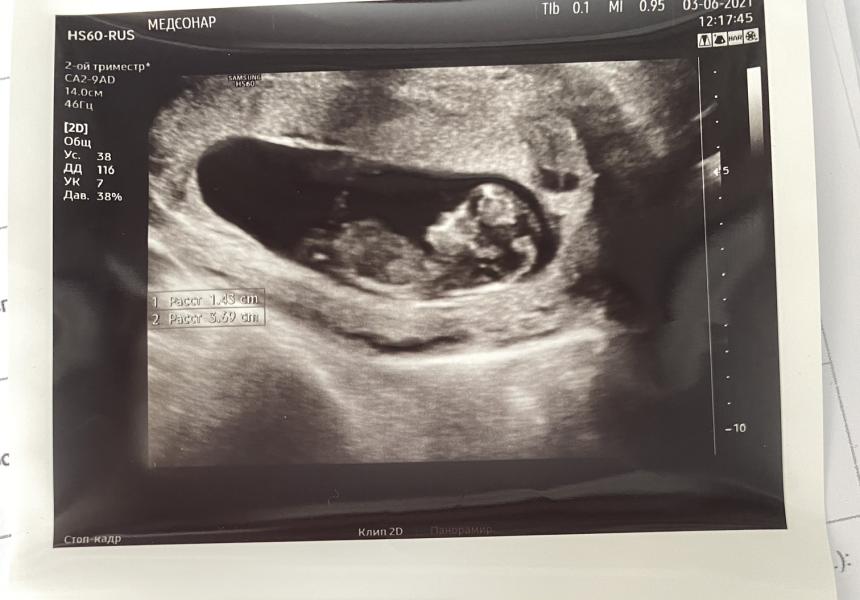

Сегодня сходила на узи в Медсонар к Ходченко Ивану Анатольевичу...не смеялась так давно, как с ним😁🥰

Очень весёлый и приятный мужчина, чувствую теперь я променяю ОКСИ на Ходченко(он ещё в Екатерининской принимает) 😍

Нам уже 11 н. 2д. Подросли до 4,5 см 📏

В прошлую неделю ЧСС был аш 183, и я немного переживала,но тогда там таааакие танцульки были,поэтому сказали что все Норме. Сегодня же мы были в меру активные, прям с ума не сходили,но все же веселились😅 ЧСС 162